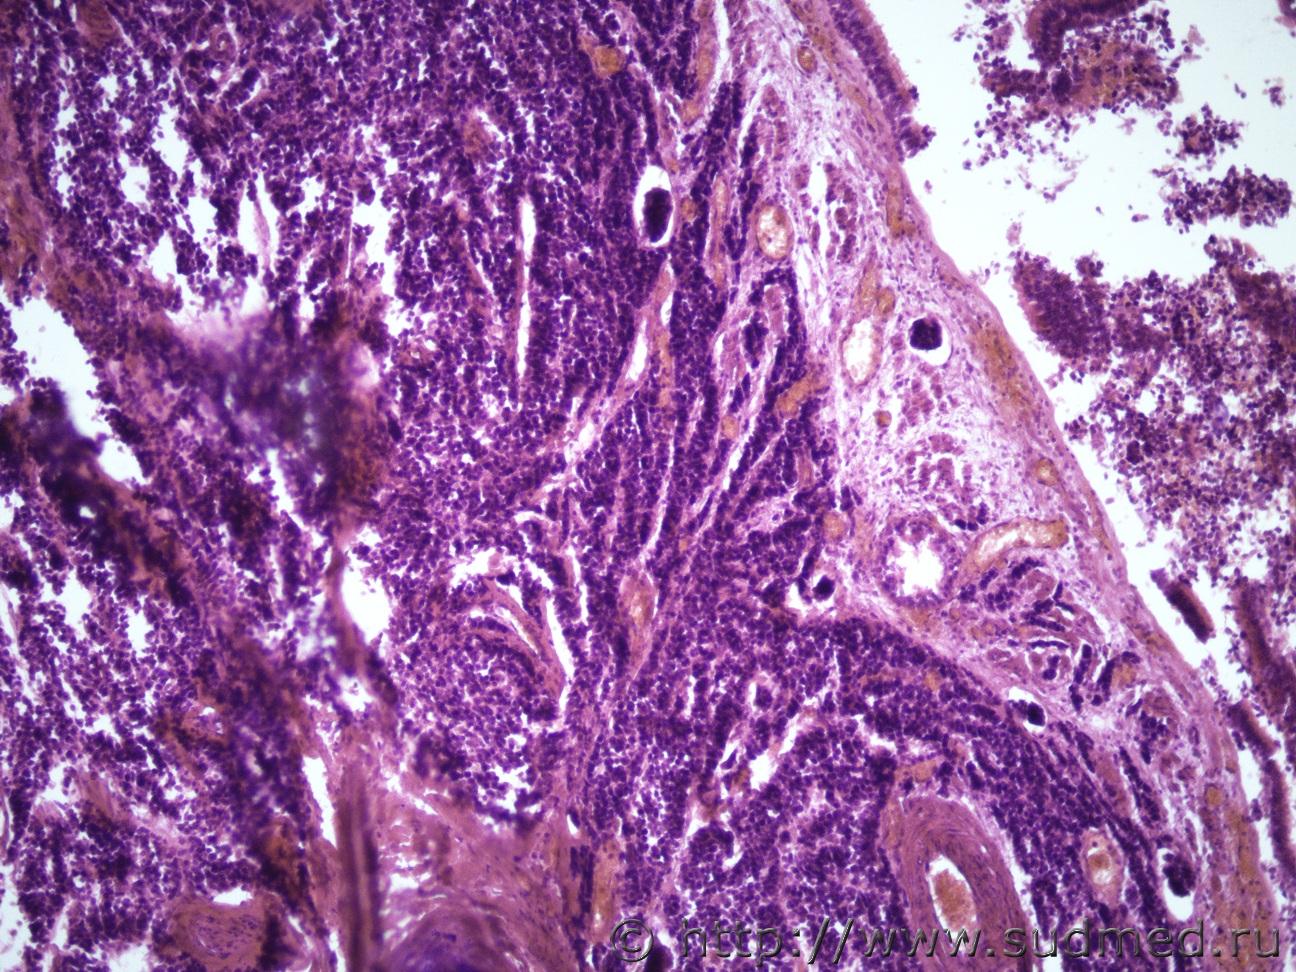

Ув. коллеги и снова здравствуйте. Как всегда опухоль. Макро- опухоль поджелудочной железы с прорастанием в окружающую клетчатку с метастазами в перибронхиальные, перипортальные ЛУ, в прикорневые отделы легких, в стенку желчного пузыря, тонкого кишечника. Легкие Судебная медицина - Прикрепленное изображение Судебная медицина - Прикрепленное изображениеСудебная медицина - Прикрепленное изображениеСудебная медицина - Прикрепленное изображение, перибрЛУСудебная медицина - Прикрепленное изображение ПЖ Судебная медицина - Прикрепленное изображениеСудебная медицина - Прикрепленное изображение , печеньСудебная медицина - Прикрепленное изображение Судебная медицина - Прикрепленное изображение Судебная медицина - Прикрепленное изображение Судебная медицина - Прикрепленное изображение Судебная медицина - Прикрепленное изображение, тонк кишСудебная медицина - Прикрепленное изображение

Наиболее подходит нейроэндокринный рак

Спасибо, рассмотрю этот вариант. Я все думала может НД протоковая аденокарцинома или мелкоклеточный рак.

Солидарен.

Непохоже.